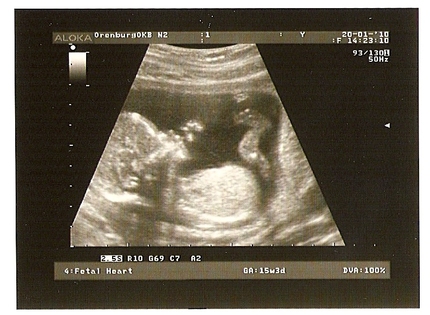

УЗИ на 15-й неделе беременности

Малышу уже 15 недель, что происходит с ним на этом сроке? Он весит уже 70 г, а в длину может достигать 10 см.

Плод в 15 недель становится все более подвижным и гибким, его движения скоординированы, он уже может сосать пальчик на руке.